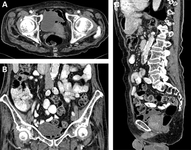

Emphysematous cystitis: (A) horizontal CT slice showing increased emphysema, (B) coronal CT slice showing increased emphysema, (C) sagittal CT slice showing increased emphysema

Middela S, Green E, Montague R. Emphysematous cystitis: radiological diagnosis of complicated urinary tract infection. BMJ Case Rep. 2009; doi:10.1136/bcr.05.2009.1832. Used with permission